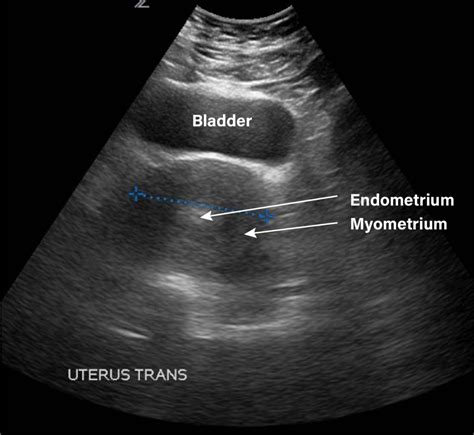

When it comes to gynecologic ultrasounds , there isn’t just one way to do things. Doctors typically choose the method that will give them the best view of the area they’re concerned about. The two main types are transabdominal ultrasound and transvaginal ultrasound . Let’s break them down. The transabdominal ultrasound is probably the one most people picture. Here, the technician applies a gel to your lower abdomen and then moves a transducer (the wand-like device) over the skin. This method provides a broader view of the pelvic organs and is often used when you have a fuller bladder, which helps push the organs up and away from the pelvic bone, making them easier to see. It’s great for getting an overall look at the uterus and ovaries, especially if there’s a concern about a large mass. Now, the transvaginal ultrasound is a bit different and often provides more detailed images of the uterus and ovaries. For this type, a smaller, covered transducer is gently inserted into the vagina. Don’t worry, guys, it’s usually not painful, just a bit strange feeling for some. This method allows the sound waves to get closer to the organs, resulting in clearer, more magnified images. It’s particularly useful for examining the uterine lining, detecting small fibroids or cysts, and evaluating early pregnancy. Sometimes, your doctor might recommend a combination of both to get the most comprehensive information. There’s also a specialized type called a 3D ultrasound , which can create more realistic, three-dimensional images of the pelvic organs. This can be helpful in diagnosing certain congenital abnormalities of the uterus or providing more detailed views of fibroids. Finally, there’s the Doppler ultrasound , which is often used in conjunction with other types. This technique assesses blood flow within the pelvic organs, which can be important in evaluating conditions like ovarian torsion or assessing blood supply to tumors. Each type has its strengths, and your healthcare provider will select the best approach for your specific needs.

Alright, let’s walk through what happens during your gynecologic ultrasound appointment. First off, try not to be nervous, guys! The technicians are professionals, and their main goal is to get the best images possible to help your doctor diagnose you. When you arrive, you’ll likely check in and then be shown to an examination room. You’ll be asked to undress from the waist down and cover yourself with a sheet or gown. As we mentioned, the first part might involve a transabdominal ultrasound . The technician will apply a warm, clear gel to your lower abdomen. This gel is crucial because it helps the transducer glide smoothly and eliminates air pockets between the transducer and your skin, allowing the sound waves to travel effectively. Then, they’ll press the transducer against your abdomen and move it around, tilting and angling it to get different views. You might feel some pressure, but it shouldn’t be painful. They’ll look at your uterus, ovaries, and other pelvic structures. After the transabdominal scan, if a transvaginal ultrasound is needed, you’ll likely be asked to empty your bladder. The technician will then cover a smaller, slender transducer with a protective sheath (often with a bit of lubricant) and gently insert it into the vagina. Again, this might feel a little strange, but it’s generally not painful. They’ll maneuver this transducer to get very close-up, detailed images of your uterus, cervix, and ovaries. You’ll usually be able to see the images on a screen nearby, though it might look like a black and white fuzzy picture to you – the technician knows what they’re looking for! The whole process typically takes about 20 to 40 minutes, depending on what the doctor needs to see. After the scan, you can get dressed, and the technician will process the images for the radiologist to interpret. The radiologist will then send a report to your doctor, who will discuss the results with you at a follow-up appointment. It’s a pretty straightforward procedure, designed to gather essential information about your reproductive health.